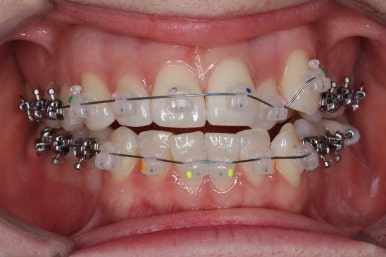

이번 환자분께서 사용하게 될 장치는 데이몬 클리어라는 세라믹 자가결찰 장치입니다.

세라믹 장치 중 대표적인 장치가 데이몬 클리어, 엠파워 클리어, 클리피씨 등이 있는데 부산부정교합 키다리아저씨치과에서는 데이몬 클리어와 엠파워 클리어를 주로 사용합니다. 약간의 부피감이 차이가 있고 세라믹 함량의 비율이 조금 차이가 납니다.

부산부정교합 키다리아저씨치과에서 장치를 처음 부착한 모습입니다.

많이 삐뚤어진 부위는 철사가 굽이굽이 지나가는 것을 볼 수 있습니다. 이 철사가 점점 직선으로 가지런해지면서 치아가 바르게 가지런해집니다.